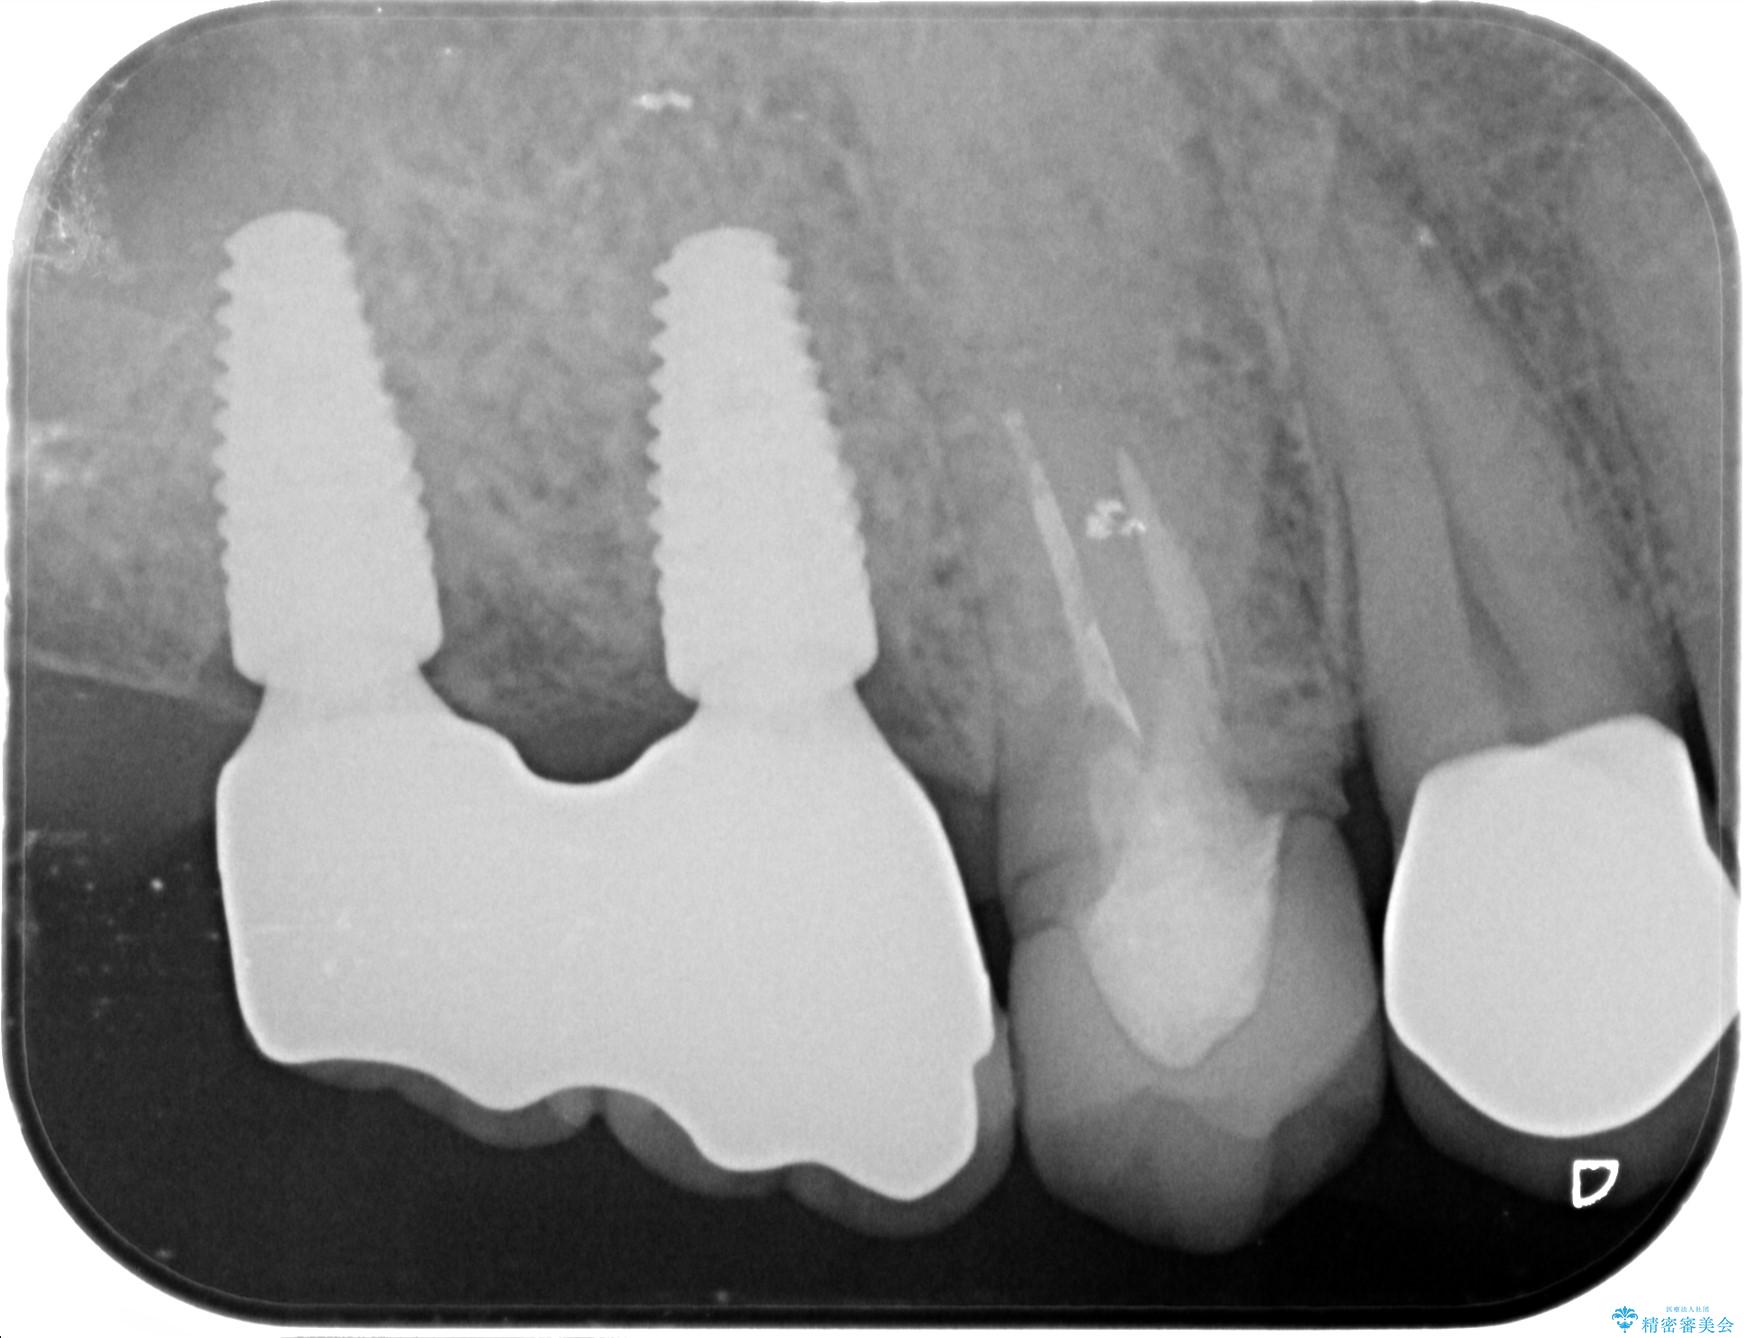

- 歯を抜いたまま放置してしまい、「やはりしっかりと噛めるような状態にしてほしい」とインプラント治療を希望され来院されました。

人工歯根であるインプラントを埋入することで奥歯でまたしっかりと噛める咬合機能を回復します。

- 88万円(インプラント×2・仮歯×2・チタンカスタムアバットメント×2・ジルコニアクラウン×2)費用は治療当時の料金となります